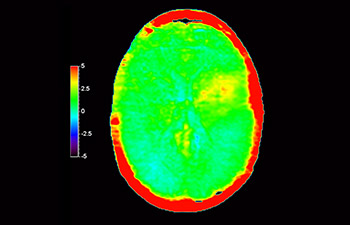

Brain lesion

with 3D APT